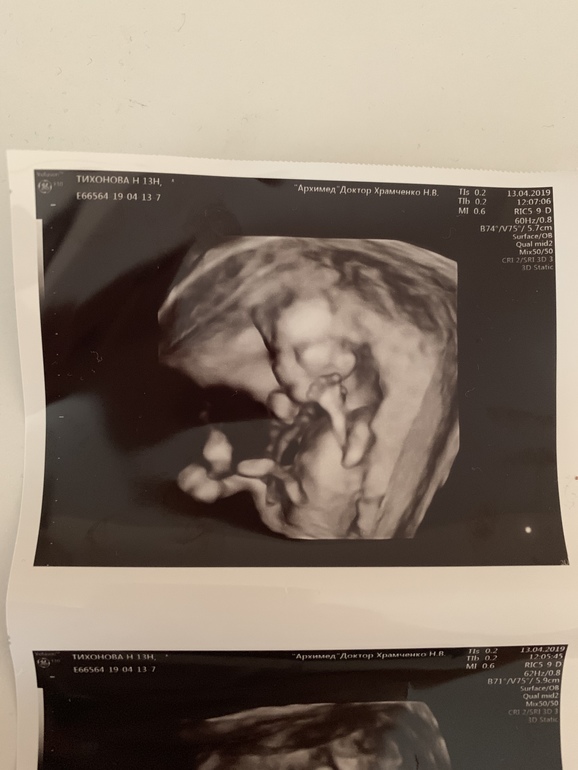

Первый скрининг платно. (13.1нед)Фото малыша ❤️

И фото ляльки